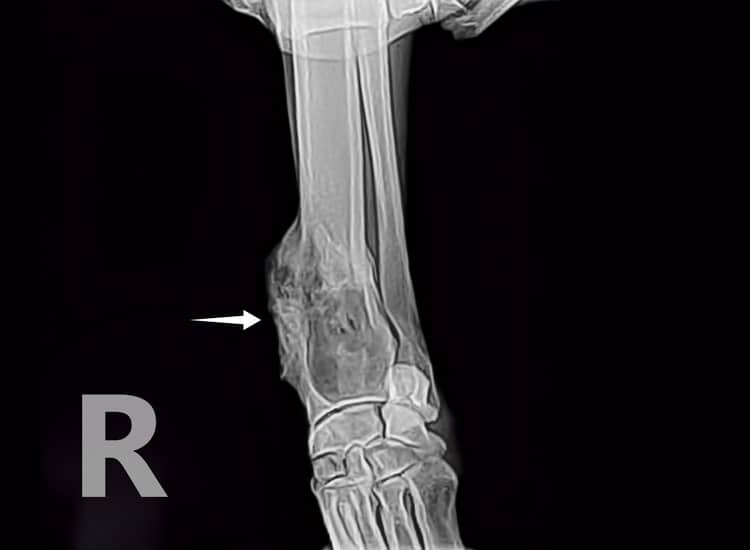

Radiographie d’un ostéosarcome sur le radius d’un chat

Le diagnostic radiographique d’ostéosarcome est envisagé en présence d’un mélange de lésions lytique (destruction de l’os) et proliférative (prolifération osseuse) mais il est également possible d’observer ce type d’image avec d’autres tumeurs que les ostéosarcomes.

Radiographie d’un ostéosarcome sur un ulna (anciennement cubitus) avec lésions d’ostéolyse et de prolifération périostée

* Prolifération périostée : le périoste est la membrane qui recouvre l’os (sauf au niveau des surfaces articulaires) et permet ainsi sa croissance et sa nutrition.